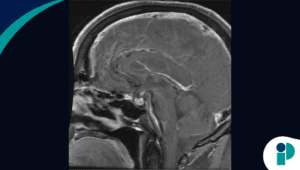

La histerectomía vaginal es un procedimiento quirúrgico para extirpar el útero a través de la vagina. Durante esta intervención, el cirujano separa el útero de los ovarios, de las trompas de Falopio y de la parte superior de la vagina, así como de los vasos sanguíneos y del tejido conectivo que lo soportan, antes de extirparlo.